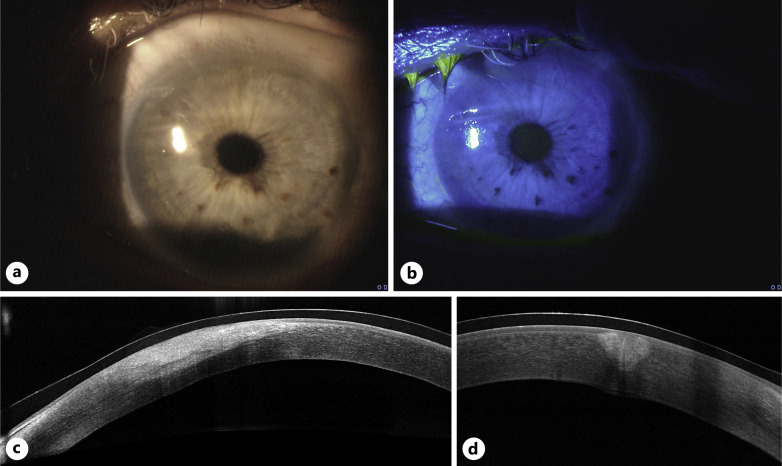

Case description: A 75-year-old man presented with unilateral diathermy-associated corneal laceration superior to the visual axis following cosmetic blepharoplasty. Vision had deteriorated from his baseline 20/30 to 20/125 postoperatively. Intervention involved multilayer AMT alongside standard care, including topical steroids and antibiotics, oral doxycycline, and vitamin C. Postoperative course was monitored with anterior segment optical coherence tomography (AS-OCT) imaging. By 3 months, complete corneal healing and restoration of baseline visual acuity were achieved.